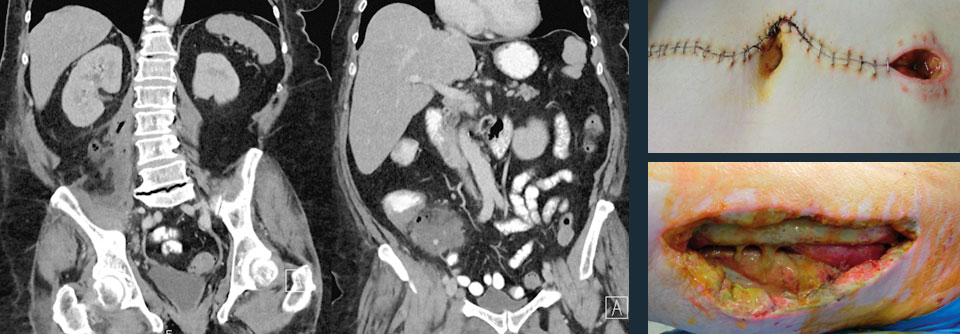

Überdurchschnittlich häufig, so ein Ergebnis der Untersuchung, erfolgte die Fehldiagnose bei Mädchen und Frauen. Auffallend oft waren zudem Patienten mit Begleit­erkrankungen betroffen. Dasselbe galt, wenn sich die Kranken mit der Symptomkombination Bauchschmerz und Verstopfung vorstellten. Alleiniger Bauchschmerz oder Abdominalschmerz plus Übelkeit schienen dagegen eindeutigere Hinweise zu liefern. Wurde bei Erstvorstellung ein CT angefertigt, stiegen die Chancen auf die richtige Diagnose. Wurde das Abdomen lediglich geröntgt, sanken sie. Was wohl damit zu tun hat, dass die Ärzte bei Anordnung der Tomographie schon den ganz konkreten Verdacht hatten, so die Vermutung der Autoren.

Auch die Sonographie gibt oft nicht die entscheidenden Hinweise: 22,3 % der Ultraschalluntersuchung bei Erwachsenen ließen die Appendizitis im ersten Anlauf unentdeckt. Dennoch sei eine CT sicherlich nicht bei allen Verdachtsfällen notwendig, meinen die Autoren. Bei ungeklärtem Bauchschmerz sollte man die Patienten aber einige Zeit im Blick behalten, so sein Rat.